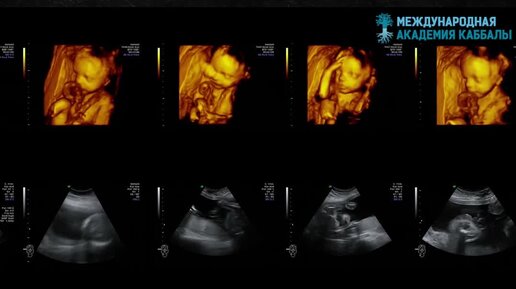

Есть ли душа у детей из пробирки?